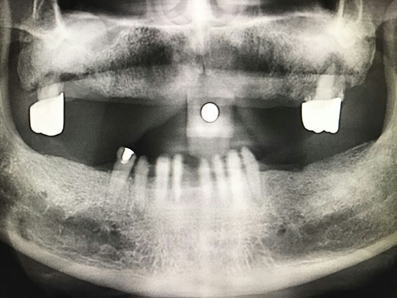

毛國(guó)斌種植病例——群討論分享